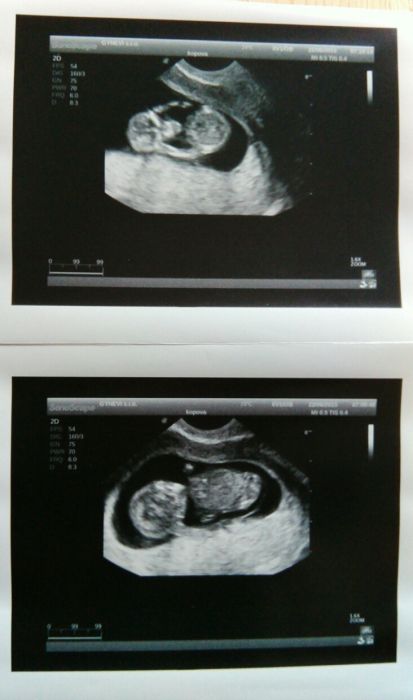

Bety,na plodovku bych nemusela jít,kdybych řekla,že nechci...je to jen na doporučrní,prvně mě to doporučil můj gynekolog a dnes mě objednával na ten screening který dělají na genetice v Plzni,a paní na druhé staně něco říkala doktoru a on na to: paní má 36let ale v době porodu jí bude 37 let...a pak jen řekl,pacientka je s tím seznámená a na odběr půjde...takže asi tak :-) Samozdřejmně že pokud by byl nějaký problém,tak na plodovku chodí i mladší maminky a hlavně ne dobrovolně ale na žádanku...ale já pro klid v duši a hlavně pro jistotu,že ten brouček bude v pořádkuprostě bez váhání jdu :-) Jinak děvčata,dnes mi dělal dr takový podrobnější utz,a po 10 minutách mi řekl,že první odhad na 60% je chlapeček :-) Ale nemám to brát vážně a na 100% :-) Tak jsem zvědavá,páč opět mám stejný pocit jako u syna...že čekám chlapečka :-) A jak jsem slíbila přikládám fotečky :-)